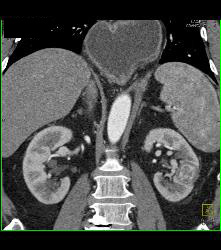

Hypervascular Left Renal Cell Carcinoma